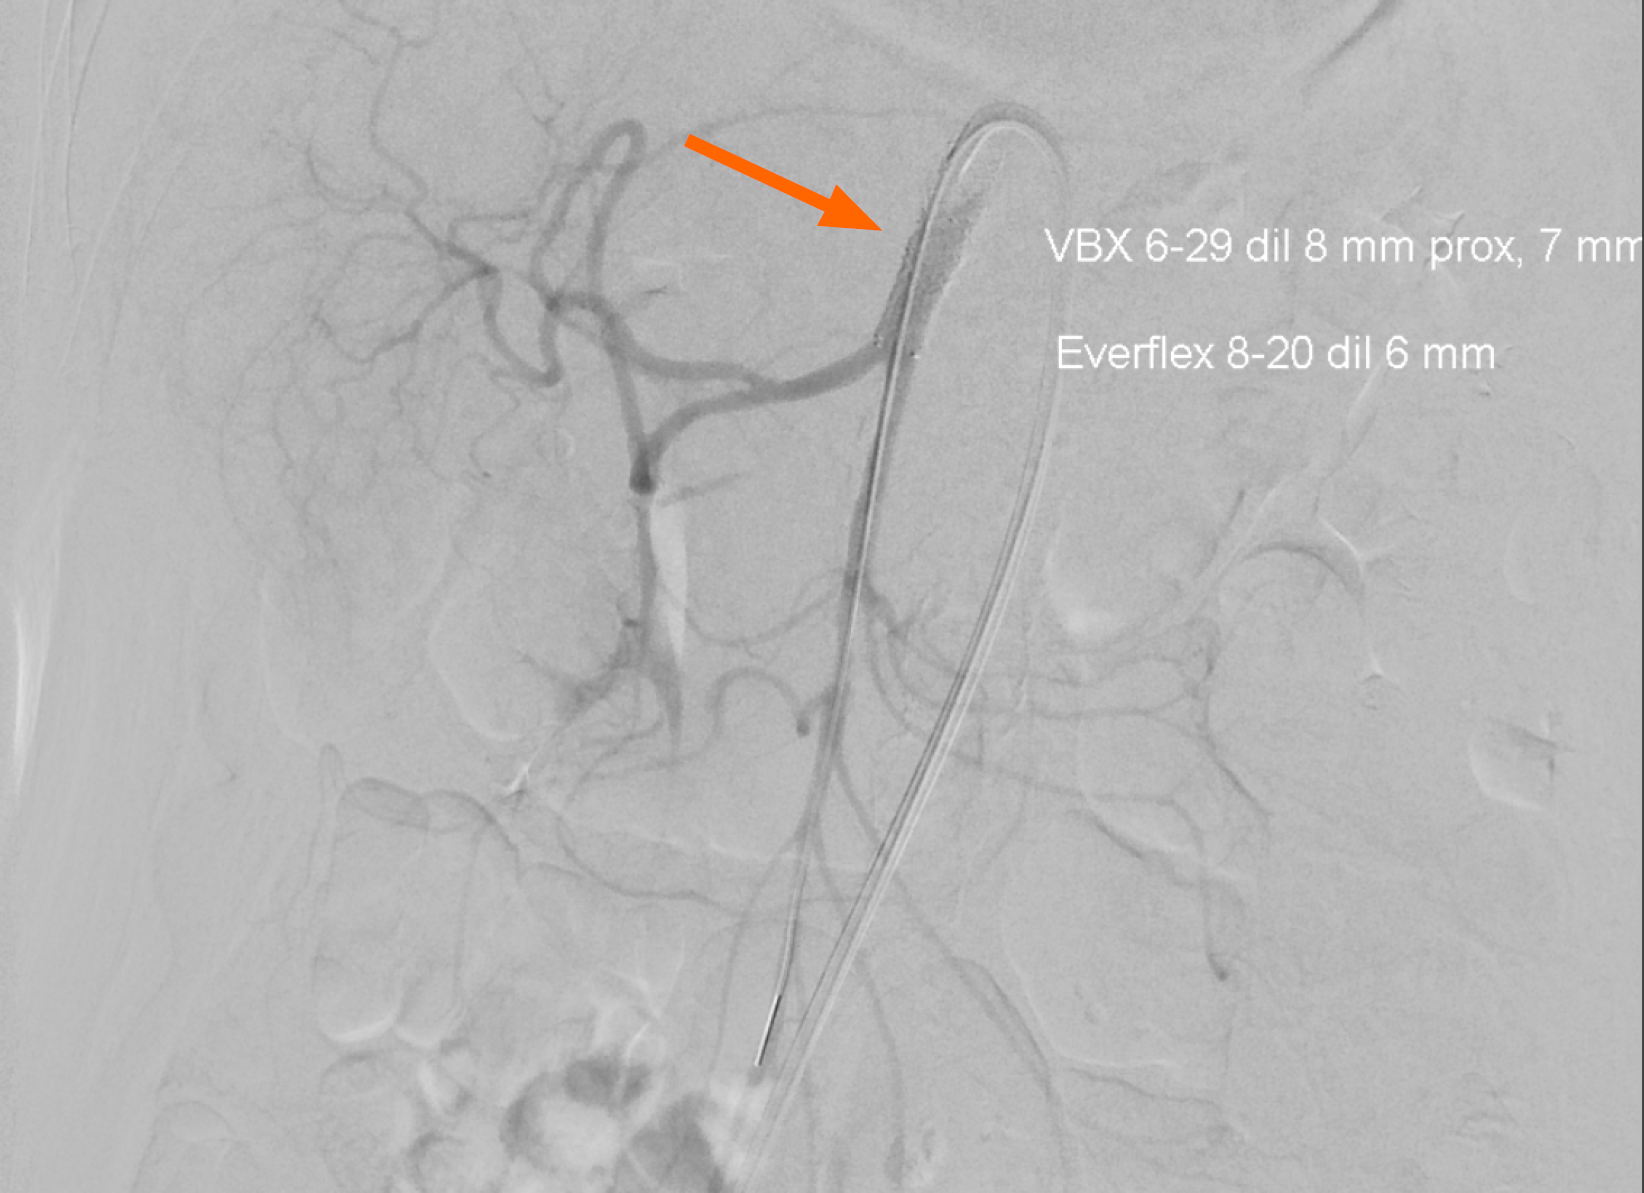

Case 1: The gastroenterology registrar re-reviewed the prior abdominal CT, which had been performed months earlier as part of the initial work-up for non-specific abdominal pain. This review revealed extensive calcifications at the origins of the superior mesenteric artery (SMA) and celiac trunk (Figure 1A and B), which had not been reported in the original radiology interpretation. CT angiography was then performed to assess the mesenteric vasculature, confirming high-grade stenosis of the SMA with suspected 1.5 cm portion of the vessel showing occlusion (Figure 1C and D). Figure 1A and B (CT abdomen protocol) show the presence of significant calcification at both the celiac trunk and SMA (Figure 1A, sagittal reconstruction), with extensive calcification at the SMA ostium when viewed in axial view. Figure 1C and D (CT angiography protocol) show extensive calcifications at both the celiac trunk and SMA, with a 1.5 cm portion of the SMA distal to the calcification showing vascular occlusion (Figure 1C, sagittal reconstruction). Figure 1D shows extensive calcification at the SMA ostium when viewed in axial view. Given the patient’s prior history of GCA, a review of the patient by a rheumatologist, alongside a positron emission tomography (PET-CT) were done to assess for the presence of clinical and/or tomographic signs of reactivation of underlying GCA. The PET-CT and the clinical exam were both negative for GCA reactivation.